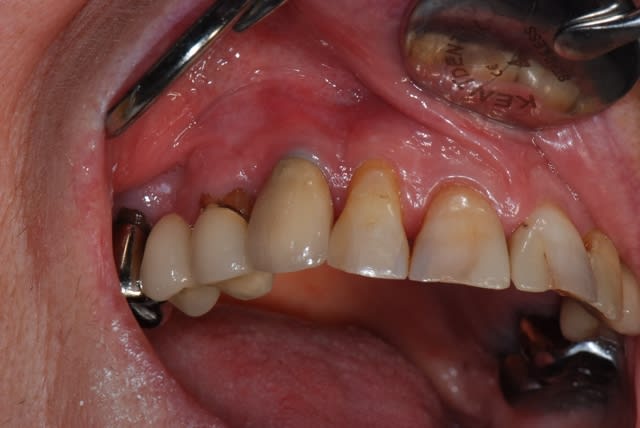

Voila, tout est dans le titre, une patient avec une dent re-implanté suite accident de voiture en 1990. Resorption externe et semble ( comme la 12 ) completement ankylosée.

Une EII, tres bien, mais tu le dis toi-même, tout dépend de l'extraction, sachant qu'en plus, il y a un sourire gingivale, faut pas se louper.